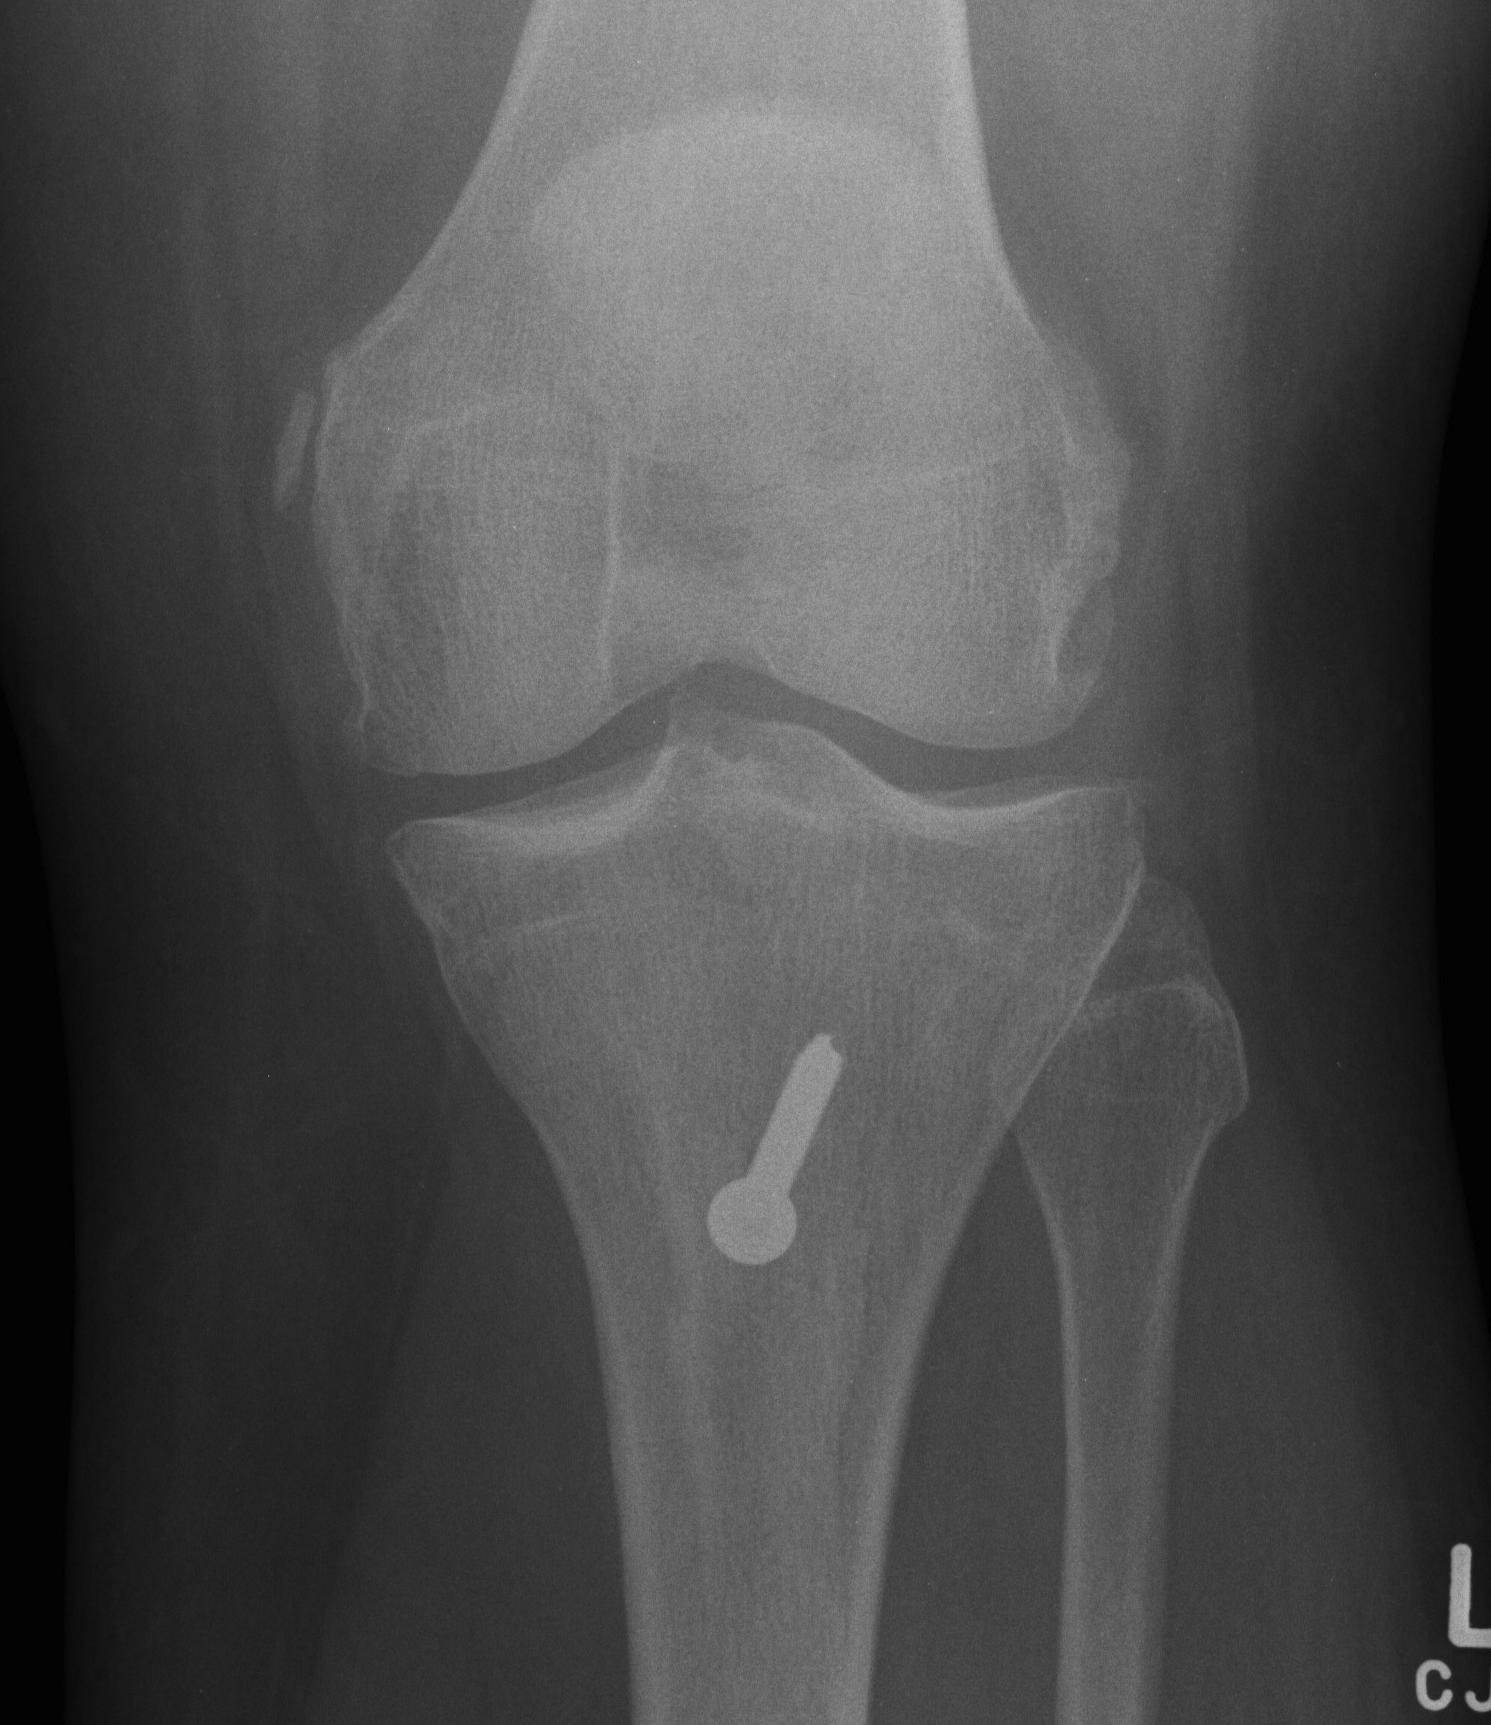

- fix with two screws

- secure with singe 4.5 mm bi-cortical lag screw